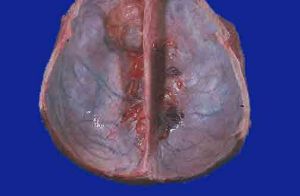

硬腦膜外血腫硬腦膜外血腫在顱內血腫中比較常見。血腫位於顱骨內壁和硬腦膜之間,由腦膜血管,靜脈竇和板障血管的破裂而引起。好發於額、頂、顳部,絕大多數的硬膜外血腫伴有顱骨骨折。硬膜外血腫主要的臨床表現是顱內壓增高症狀明顯,其最典型析症狀是受傷後立即昏迷,清醒後再次昏迷。血腫對側肢體出現無力,甚至癱瘓、失語。血腫所在側瞳孔散大,光反射減弱或消失。X線照片檢查,有時可在瞳孔擴大側發現骨折。目前CT已成為確定顱內血腫的更為準確的技術手段。硬腦膜外血腫的診斷一旦確立,有明顯頻內壓增高和腦受壓者應立即進行手術,以清除血腫、徹底止血,降低顱內壓力。